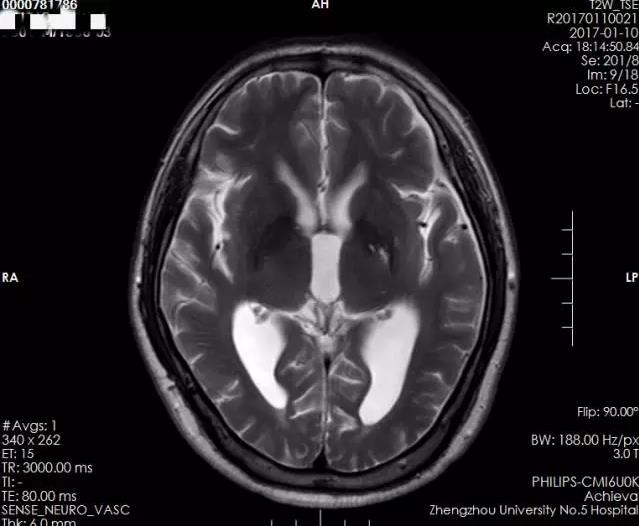

术前侧脑室、三脑室均增大,并有室旁水肿,测量三脑室大小约1.49cm

术后侧脑室及三脑室较前明显缩小,室旁水肿基本消失,测量三脑室大小约1.10cm